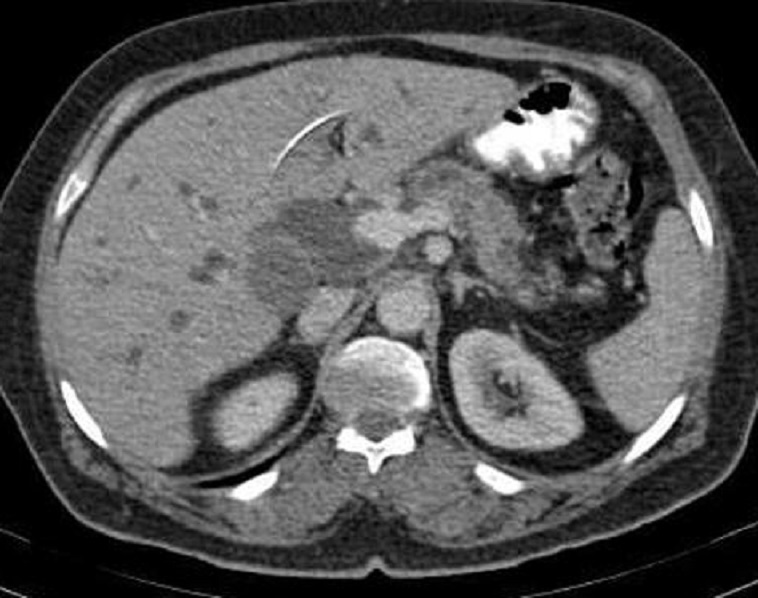

Image radiologique d'une

adenocarcinoma de la tete du pancreas ( fleche rouge

)avec signe indirect de dilatation du CPP et image

de pseudo-kyste a hypodense au queue du pancreas (

fleche jaune ) . Coupe TDM plus C+ axiale |

Image radiologique des metastase en

aspect lesionaire hypodense du foie droit ( fleche

rouge ) . Ce sont des nodule metastasique a distance

au foie droit . Image TDM en coupe axiale . |